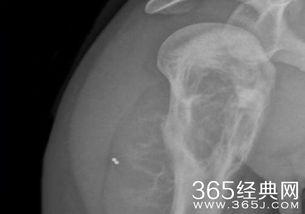

骨癌是一种恶性程度很高的癌症,治疗起来难度极大。为了对抗病魔,小李开始了漫长的治疗历程。他先后接受了化疗、放疗等多种治疗手段,承受了常人难以想象的痛苦。